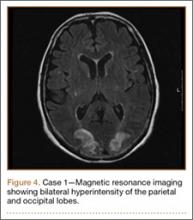

Development and Diagnosis of PRES. The patient made significant progress with physical therapy and developed episodes of hypertension at night on postoperative days 4 to 6. Her mean peak systolic blood pressure was 180 mm Hg. This improved after oral beta-blocker therapy. On postoperative day 6, the patient was ambulating with physical therapy and the aid of a walker. She was found to be neurologically intact, was resting comfortable in a chair reading a book, and was cleared for transfer to a rehabilitation facility the next day. During the morning on postoperative day 7, she developed confusion and visual loss. The patient reported blurry vision followed by complete bilateral painless loss of vision aside from mild light perception. She was unable to identify any objects. She had extinction to double simultaneous stimuli and evidence of agraphesthesia in the left hand. Her neurologic examination was otherwise at baseline. Upon emergent imaging, head CT showed bilateral symmetric areas of hypodensity involving the cortical and subcortical white matter of both occipital lobes (Figure 3). MRI showed extensive bilateral cortical and subcortical signal hyperintensity involving the parietal and occipital lobes (Figure 4). No evidence of petechial or lobar hemorrhage was found.